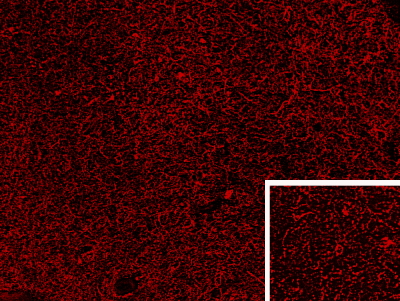

IHC Results Frozen section of Human Hypothalamus shows staining of dense enkephalinergic axon plexus and scattered neuronal cell bodies (higher magnification inset) in the human infundibular nucleus. Recommended concentration: 0.3-1µg/ml. | |